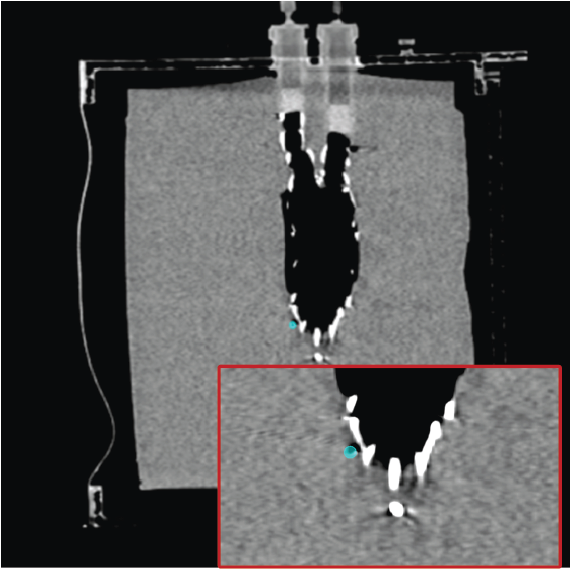

3.3.1 Evaluation on endoleak phantom

The endoleak phantom contains spinal elements, an aortic stent, a simulated aneurysm and feeding vessels, embedded in polyvinyl alcohol cryogel (PVA-C) as a tissue mimic. In the endoleak repair procedure, a needle-catheter combination is guided into the feeding and draining vessels to occlude the persistent perfusion. Fluoroscopic images were acquired under various settings, including angular rotation ( to ), orbital rotation ( to ), SIDs ( to ) and phantom motion, to evaluate the accuracy, robustness and capture range of our registration approach. The 2D X-ray images were captured with an image size of 1017 1017 pixels and a pixel spacing of \qtyproduct0.29 x 0.29\milli. Target points (20-23) were selected from the stent intersection points (see Fig. 8A). The mPD was used to measure the 2D guidance error, while the success rate (SR) was reported as the percentage of mPD measurements less than 5 mm.

3.4 Phantom experiments

A phantom targeting experiment was conducted to evaluate the accuracy of needle insertion. Fig. 9A shows the experimental setup, including an endoleak phantom, an FG mounting frame, and a Canon Alphenix C-arm (Canon Inc., Tokyo, Japan). Three magnetically tracked needles were inserted into the endoleak phantom. During 2D navigation, the tracked needles (red lines) were projected on the fluoroscopic image, while the actual needles appeared as dark lines. The discrepancies between the two were used to quantify 2D targeting accuracy.

Fig. 9B illustrates the 3D navigation, including 3D reformations, the rendered contrast-enhanced CT volume, and tracked needles. To validate 3D needle insertion accuracy, we acquired a post-insertion non-contrast CT image (Fig. 9C). The inserted needles were clearly visible in three orthogonal views, with the 3D view displaying the inserted needles in silver and the tracked needles in cyan. Needle tip and angle errors were calculated by comparing the tracked needles with their segmented counterparts from the CT image. This process was repeated three times, with a total of nine inserted needles. The overall needle insertion errors were for the tip, and for orientation, as shown in Table 5.